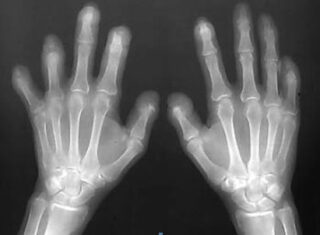

Figure. Extensive resorption and deformities in the distal and middle phalanges, especially on the left, involv-ing all the digits. The right index and ring fingers are relatively spared. Marked foreshortening of all the digits is apparent.

Ακτινολογικά, η ΑΜ χαρακτηρίζεται από σοβαρή απορρόφηση οστών και αρθρώσεων, κατά προτίμηση των ΑΦΦ και των ΕΦΦ (7). Σε αντίθεση με την ΡΑ, στην ΑΜ παρατηρείται σχηματισμός νέου οστού με ανάπτυξη ακανθών εξ έλξης, περιοστίτιδα και αγκύλωση των αρθρώσεων.

Χαρακτηριστικό ακτινολογικό εύρημα της ΑΜ είναι η παραμόρφωση τύπου «μολυβιού μέσα στη θήκη του», η οποία συνδέεται με καταστροφή της κεφαλής των μετακαρπίων με οστεόλυση και σχηματισμό νέου οστού. Η διαδικασία αυτή δημιουργεί την χαρακτηριστική κυπελλοειδή εικόνα των οστών των γειτονικών φαλάγγων (9).